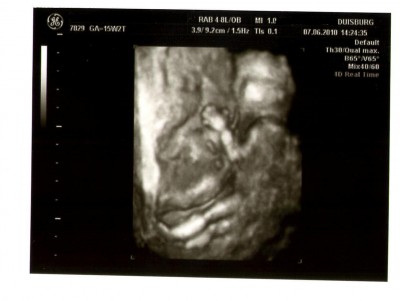

bin begeistert, dann kann ich ja auch gleich auf der ersten Seite das Madel eintragen (hach, ist dat spannend, bald wird es ja auch Wuschel-Ines und Maya79 vielleicht wissen). Freu mich sehr, das heute alles in Ordnung gewesen ist und es eurem Krümmel/Bohne gut geht!!!! Ich habe Deinen Beitrag von gestern irgendwie voll überlesen, sonst hätte ich Dir natürlich viel Glück für heute gewünscht und gelesen, das ihr 3. geworden seid beim Tunier. War noch beim letzten Tunier, als ich Dir geantwortet habe. Sorry.